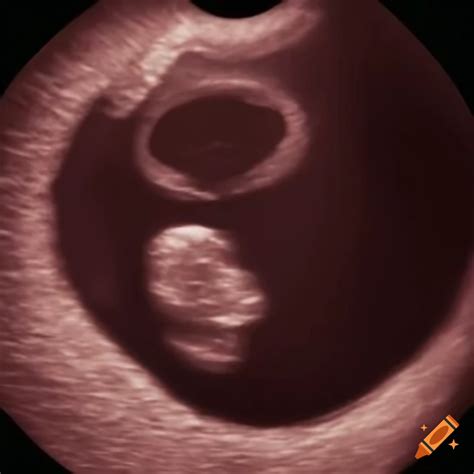

• baby at 4 weeks ultrasound

• baby at 4 weeks pregnant

• baby at 4 weeks gestation